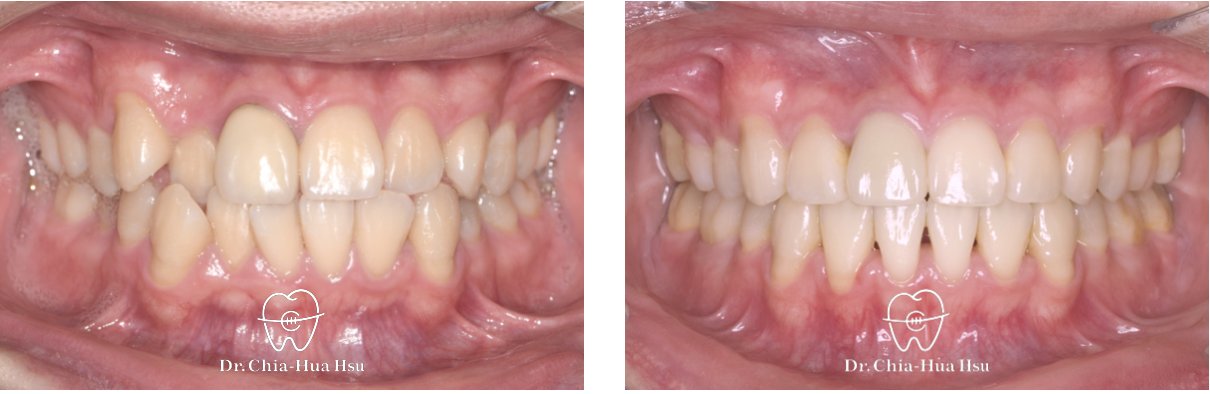

前牙錯咬、齒列擁擠

成人矯正 | ⾦屬矯正 | 拔牙治療

• 病患主訴:牙齒凌亂擁擠、笑起來不好看。

• 問題分析:患者是標準的骨骼一類咬合(Skeletal Class I)伴隨齒列擁擠以及前牙錯咬。

• 治療方式:拔除四顆小臼齒,使用傳統金屬矯正器將牙齒排列整齊、咬合緊閉。

• 治療時間:1 年 10 個月。

• 治療結果:齒列排齊,笑容更燦爛。

治療前

治療後